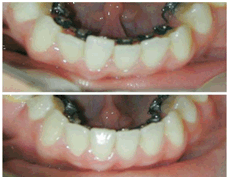

Misplaced/Maligned teeth or an “improper bite” can not only detract from people’s smiles; but may also lead to tooth decay, gum disease and eventual early tooth loss. For these, among other reasons everyone should have an orthodontic check-up at least once, the ideal age for which would be 7-15 years, though age is not a bar for treatment with braces. At Precision Dental Care we complete the treatment in minimum time period i.e. 8-12 months.

The orthodontist will assess the teeth that need to be aligned and create either a fixed or removable brace, which can be adjusted during the course of the treatment to achieve the desired effect. The fixed braces, as their name implies, are permanent fixtures and are removed at the end of the treatment period, whereas removable braces can be taken off for eating and cleaning but are generally worn at all other times. Braces will improve the function of the teeth and the general appearance of the person.